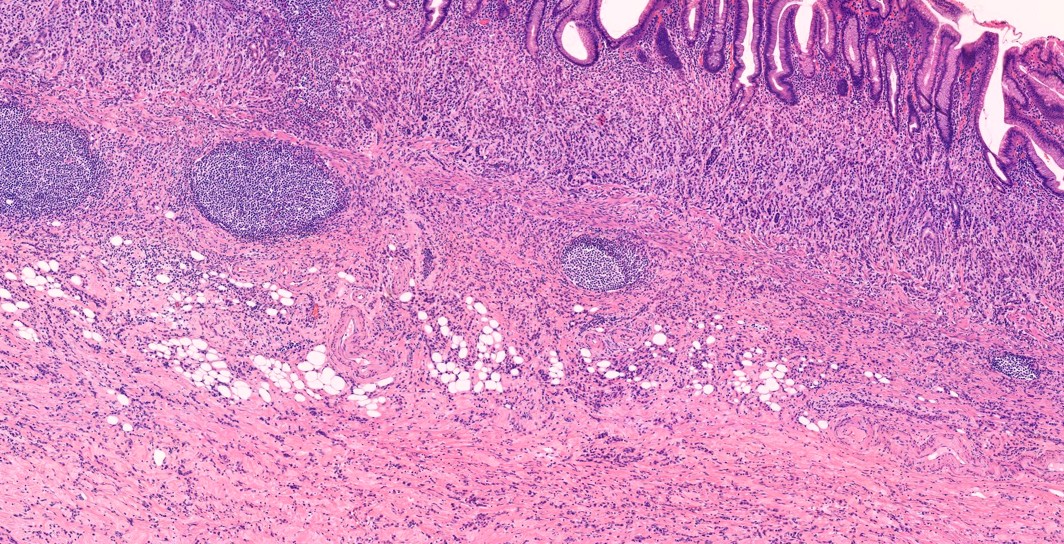

Diffusely infiltrative poorly cohesive cells.

Atrophic mucosa without cancers